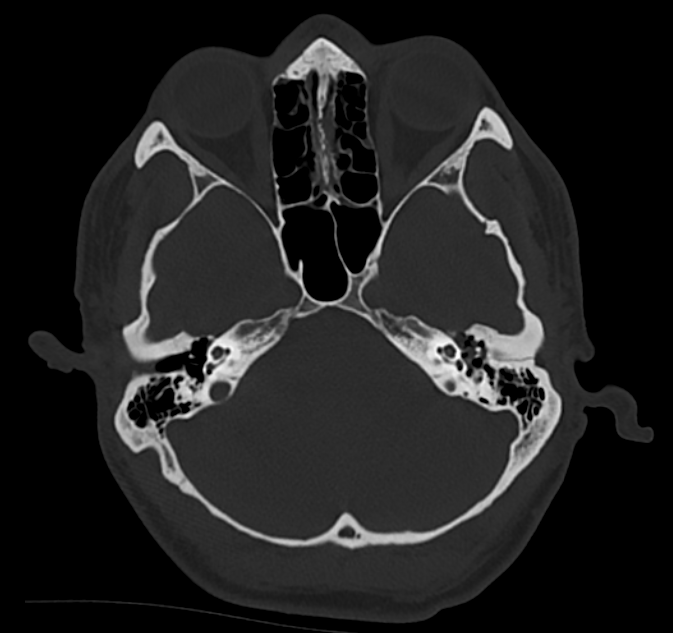

3. Petrous temporal bone fracture (left)